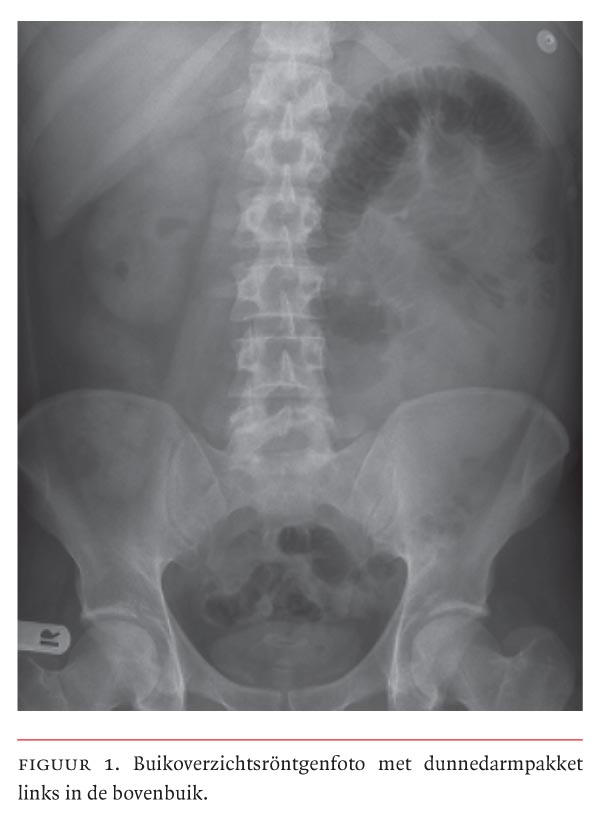

Een buikoverzichtsfoto toonde een dunnedarmpakket linksboven met geringe distensie (figuur 1). De thoraxfoto liet geen afwijkingen zien. Patiënt werd opgenomen en enkele uren later geopereerd onder het beeld van een hoge dunnedarmobstructie. Bij laparotomie bleek het grootste deel van de darmen vliezig omhuld links in de bovenbuik te liggen (figuur 2). Enkele lissen binnen het vlies waren bleek, andere donkergekleurd. Bij nader onderzoek leek een breukzak uit te gaan van een band bij het duodenum of een deel van het mesocolon; deze breukzak omhulde ongeveer 2,7 m dunne darm. Er lag nog circa 1,5 m dunne darm vrij in het abdomen. Bij het doornemen van deze band en het weghalen van een deel van de breukzak ontstond een anatomisch niet-afwijkende situatie – behoudens een brede basis van het mesenterium, waarin normaal pulserende vaten verliepen. De uitgezette dunnedarmlissen kleurden goed bij.